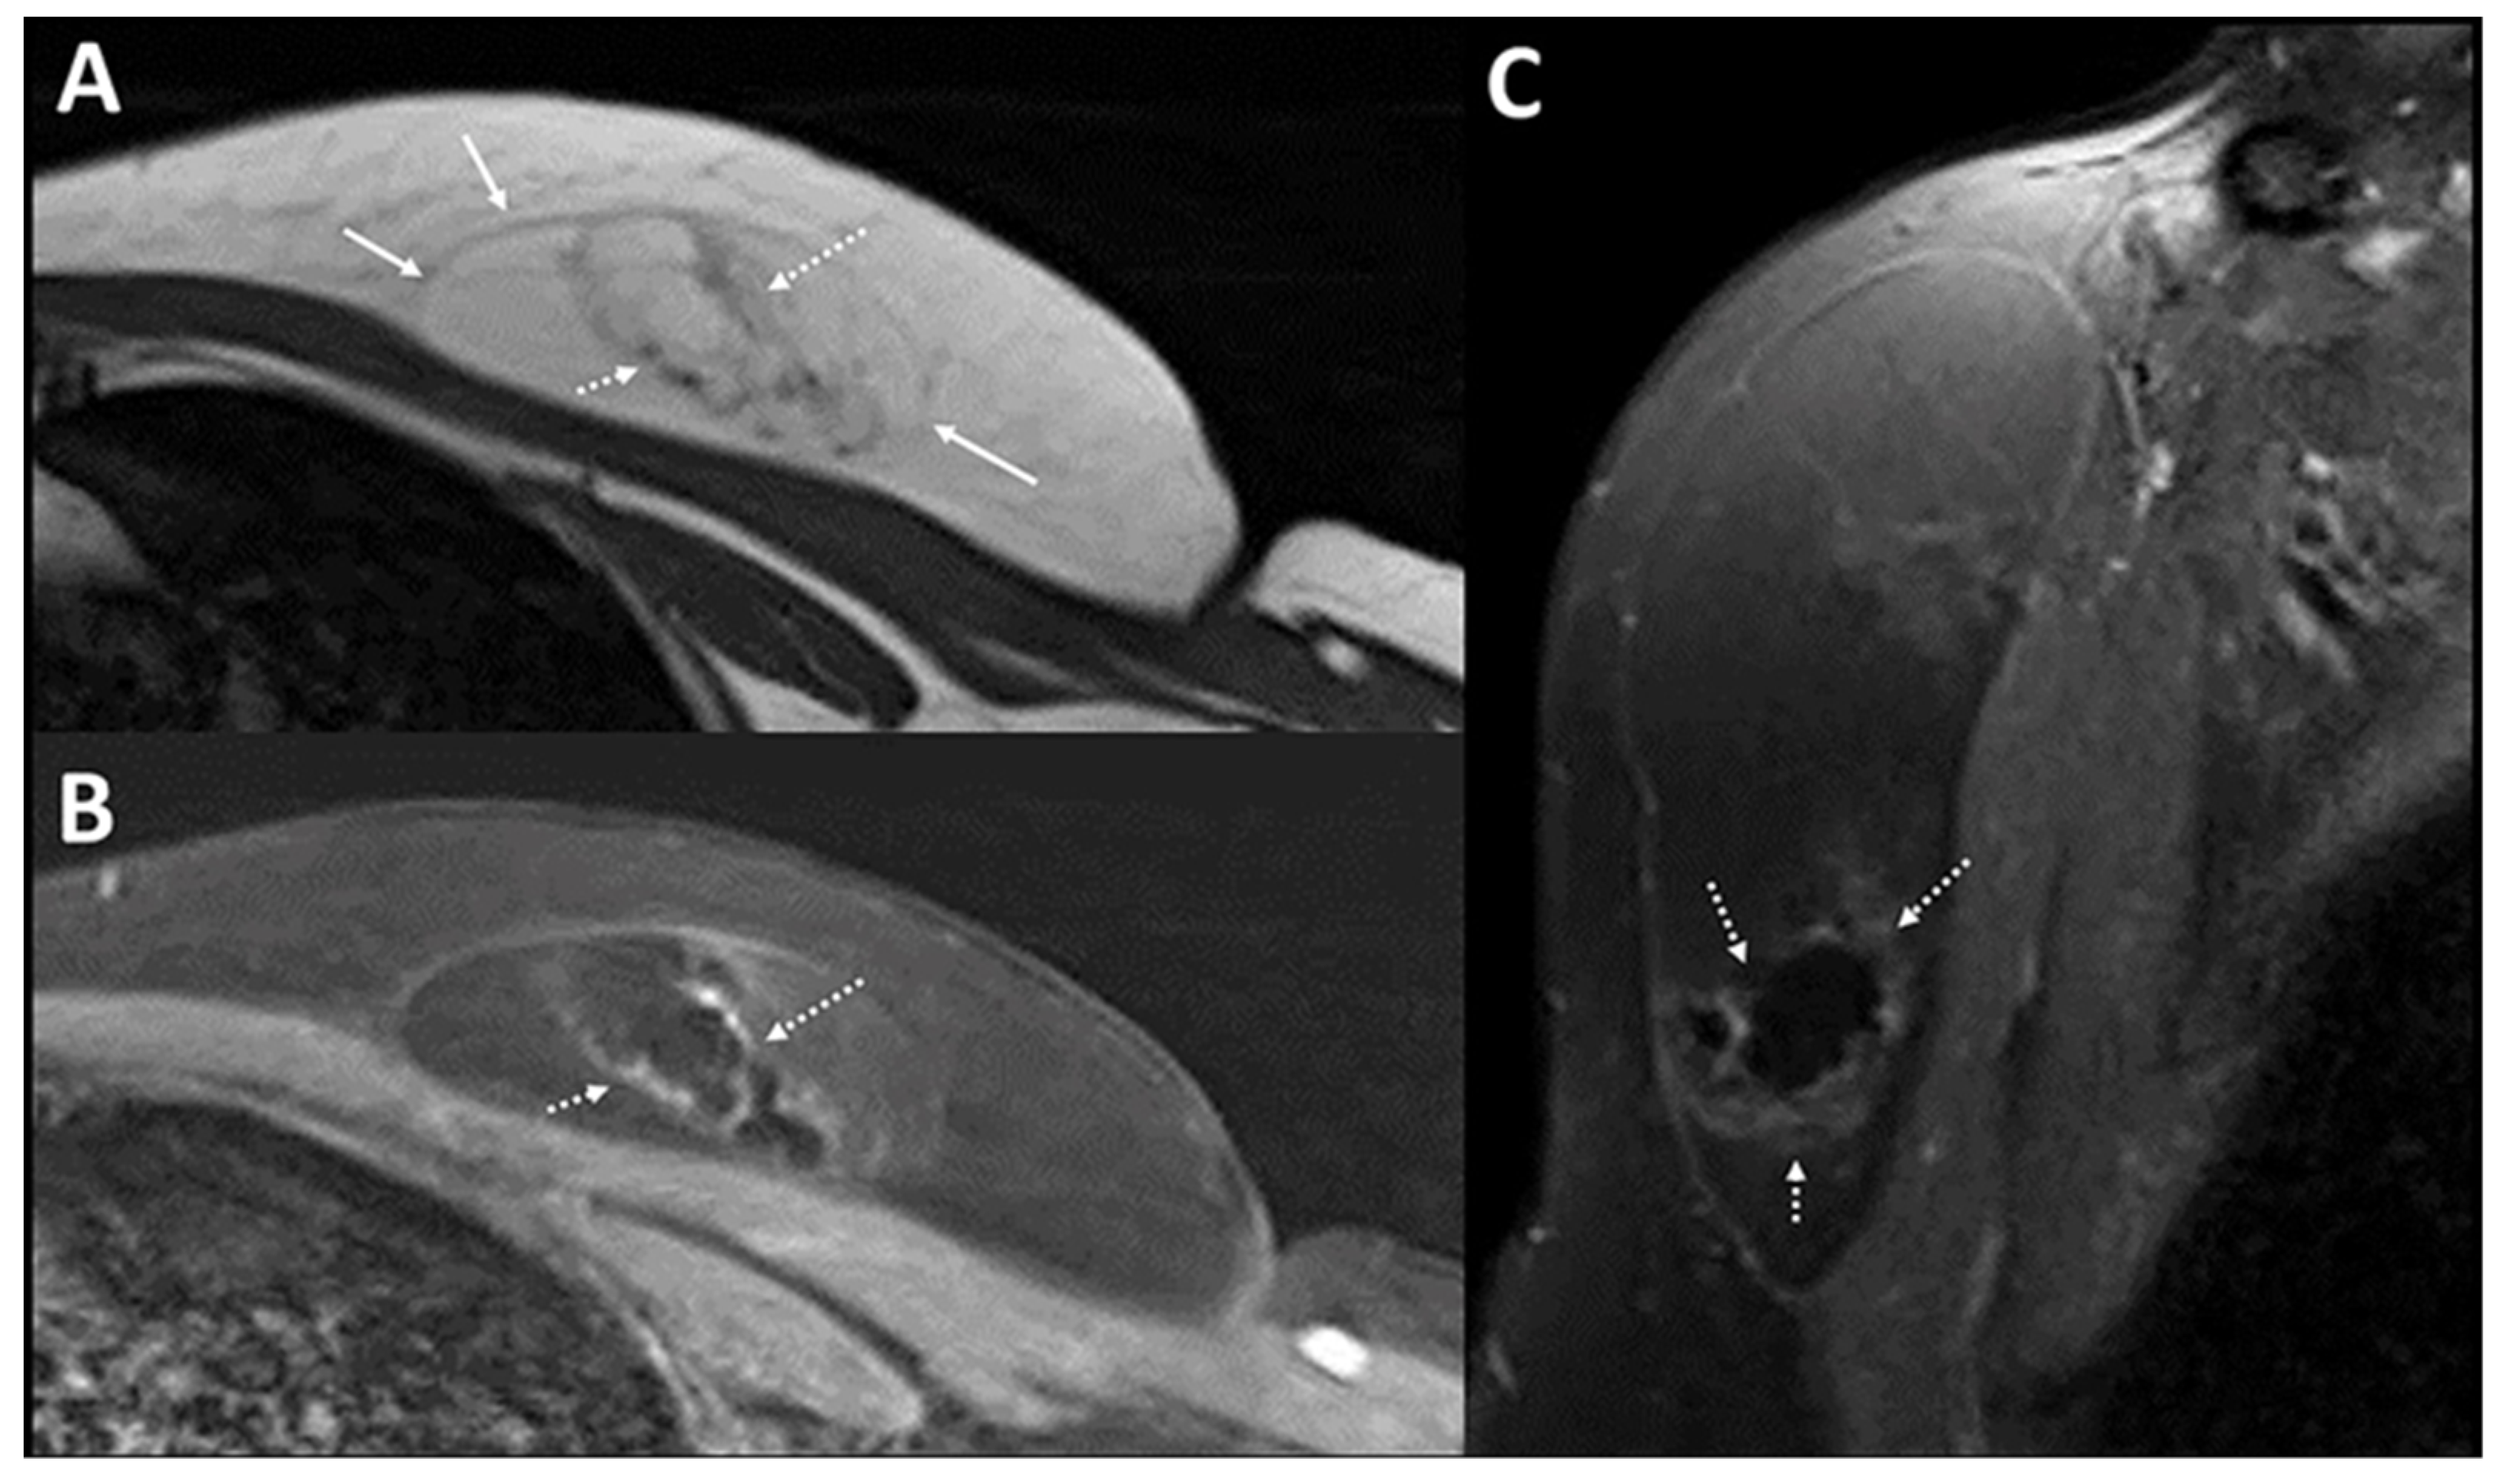

- Goh, Y.; Balasundaram, G.; Tan, H.M.; Putti, T.C.; Tang, S.W.; Ng, C.W.Q.; Buhari, S.A.; Fang, E.; Moothanchery, M.; Bi, R.; et al. Biochemical “decoding” of breast ultrasound images with optoacoustic tomography fusion: First-in-human display of lipid and collagen signals on breast ultrasound. Photoacoustics 2022, 27, 100377. [Google Scholar] [CrossRef]